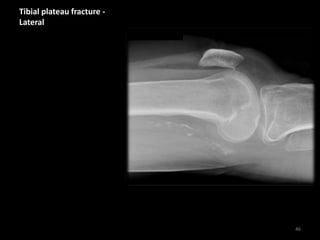

Tibial plateau fracture -

Lateral

• No visible fracture

line

• Depressed tibial

plateau contour

(arrow)

• Lipohaemarthrosis

(fat and blood in the

joint)